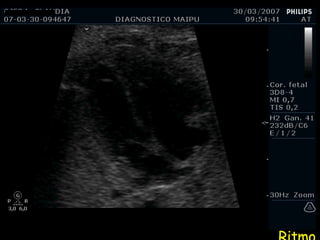

Ritmo